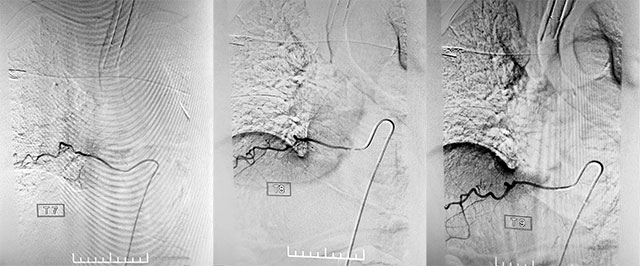

找到病灶只是手术的第一步,接下来还需要找到具体瘘口,张琪博士团队采用半椎板入路,硬膜下切开1cm小口,在长时间的血流高压下,显微镜下的血管已经迂曲增粗,相当于要在这个“面”上找出这个“点”。张琪博士团队决定使用一种特殊的材料——美蓝(一种无毒性的染料,它的氧化型呈蓝色,还原型无色),终于成功找到血管畸形点。接下来予以电凝后分离静脉、切除瘘口。切断后再次复查造影,静脉未再显影,瘘口顺利封闭,手术成功了。

▲ 复查造影,静脉未再显影,瘘口顺利封闭